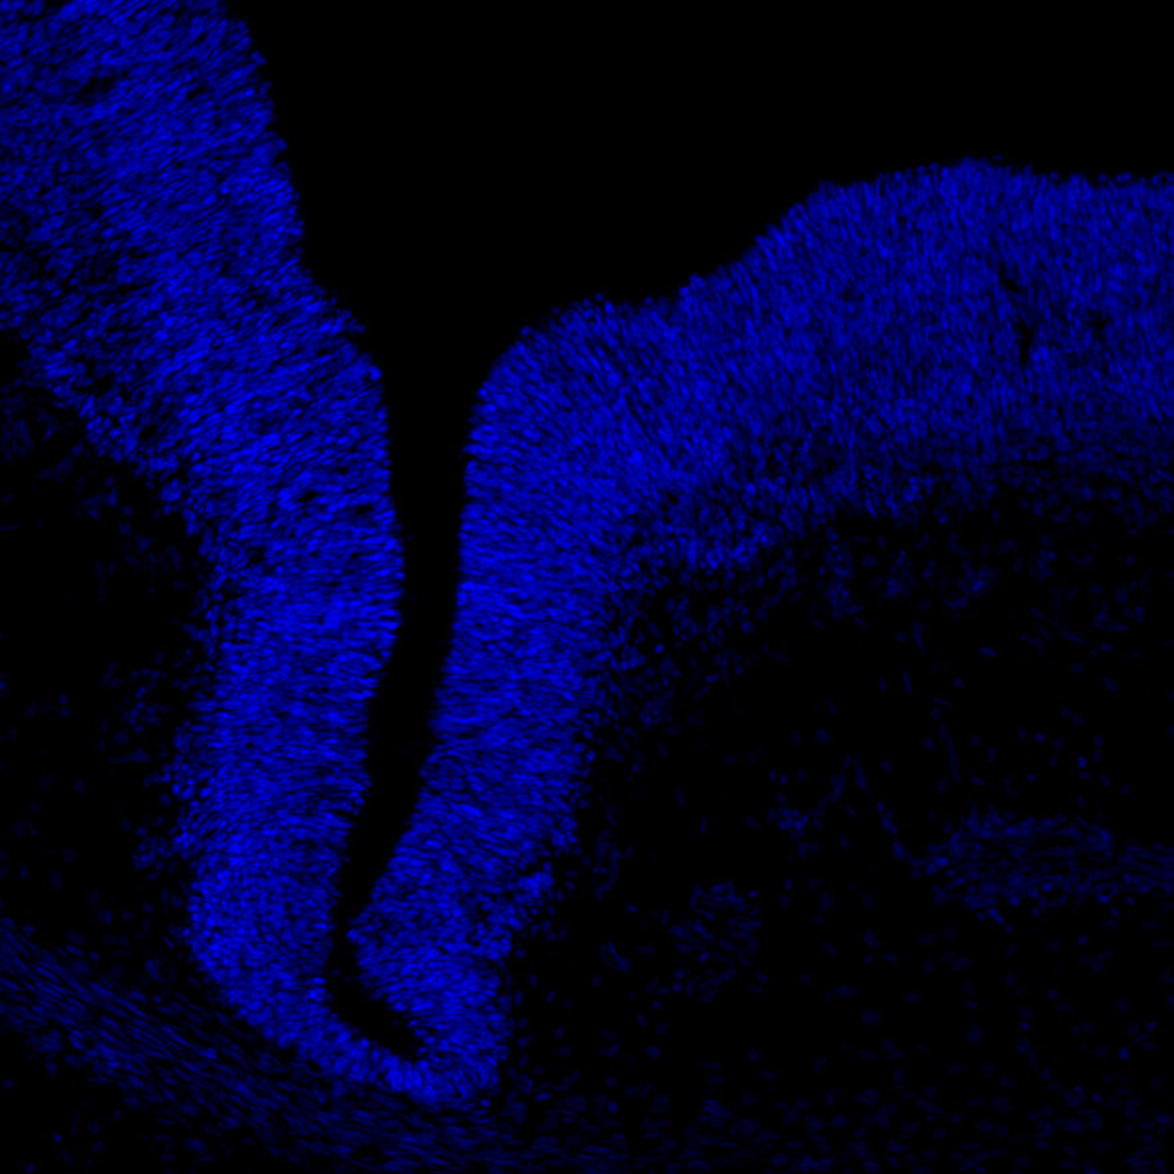

DAPI

6PCW human midbrain